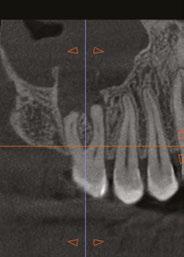

On a recent second molar case where I did not take a 3D scan prior to root canal treatment, the patient returned several days later still in pain! I took a scan and appreciated their deep split, forked in the last 5 mms of the distal canal (Figure 8). Without a CBCT scan, it’s easy to miss — I did! CBCT helps prevent this from happening by catching those variants and hard-to-find issues, which are not as rare as we think. This was another case that helped shape my current imaging protocol, so that now I scan nearly all of my patients. I honestly can’t imagine practicing without my CBCT unit — similar to when the microscope was introduced to endodontics.

Figure 7: Planned-for access with the scan info on this extremely calcified canine Figures 8 and 9: 8. Deep distal split with PARL. 9. Missed buccal canal; history of previous RCT, post, crown and apico Figure 10: Retreatment consultation. PA from GD Figure 11: Scan images show a previously existing strip perforation

what the literature suggests. And, when I know how many and where the canals are (Figure 13), I can take measurements on the scan and work more efficiently — measuring my working lengths of each canal, appreciating severe curves or calcifications, and knowing where canals can be expected to be located, again, rather than removing unnecessary tooth structure to find if it is there, or not!

As an endodontist, I often treat heavily restored teeth. I am often planning my accesses based on the scan’s information. This saves time and conserves more tooth structure. I’m not looking for canals that may or may not be there, and I’m looking for canals under the targeted/planned access — with the scan, I have an actual map (Figure 7)! CBCT directs me where to go and where to end. It reveals anomalies, which are more common than we think, so I can avoid iatrogenic incidents and provide less invasive treatments. Lower second molars with only two canals occur — often!

I’m also changing my treatment plans based on the data from my CBCT. Sometimes I look at a root canal treated PA and presume I know what I will do: a retreatment or an apico. Another recent, poignant case: a lower incisor with a previous RCT and a previous apico (Figure 9). Usually, once a tooth has had an apico, there may not be much left to offer and most of the time, the default is another apico, especially as there was very little room for an implant on the lower anteriors. I scanned the tooth and saw that a whole canal had been missed — twice! The RCT and the apico had left the buccal canal completely untouched. I changed my treatment plan based on this information!

Cracked teeth are also quite prevalent (Figure 12). Of course, I can suspect them clinically and with transillumination and other tests, I’m fairly confident in my diagnosis. Thankfully, the 3D scan proves it and shows the depth of these cracks and the angular defect. Without a CBCT, sometimes these cases are started unnecessarily.